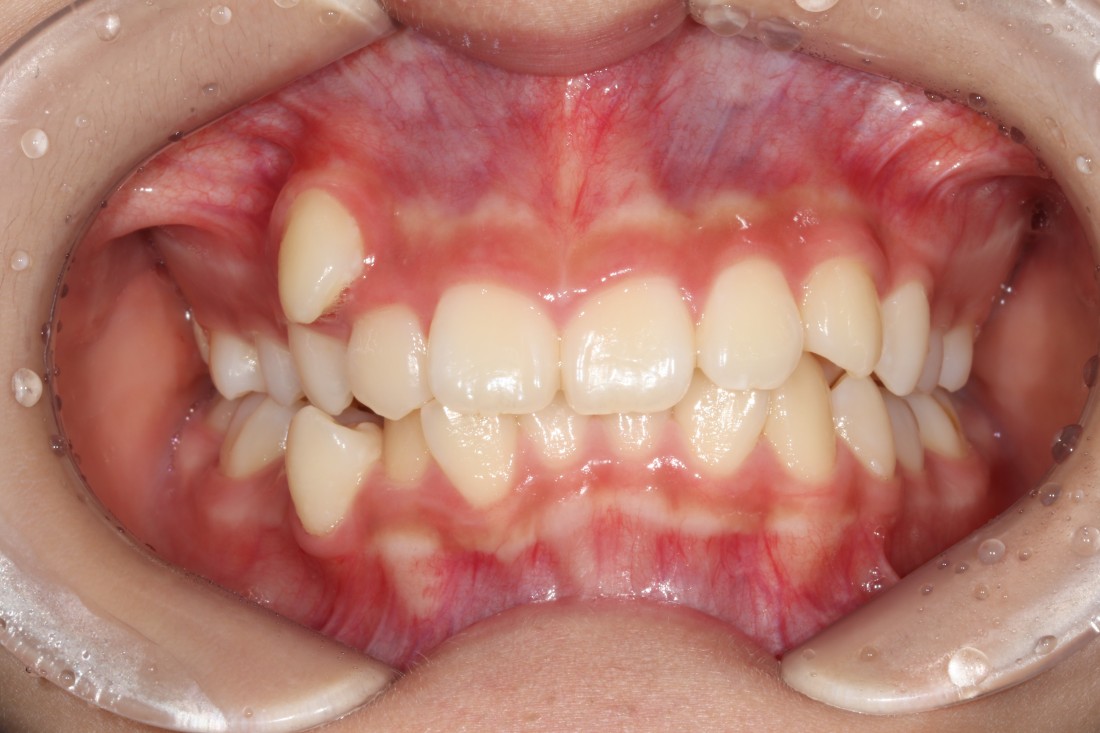

광주 발치교정이 필요한 대표적인 케이스는

돌출입의 경우인데요.

위, 아래 입술이 튀어나와 있거나

웃을 때 잇몸이 많이 보이는 경우,

혹은 입을 다물었을 때

턱에 힘이 많이 들어간다면

돌출입을 의심해볼 수 있습니다.

이런 경우에도 치아가 전체적으로

앞쪽으로 위치해서 입술을 밀어내고 있기 때문에

공간을 확보하기 위하여

광주 발치교정을 진행하는 케이스입니다.